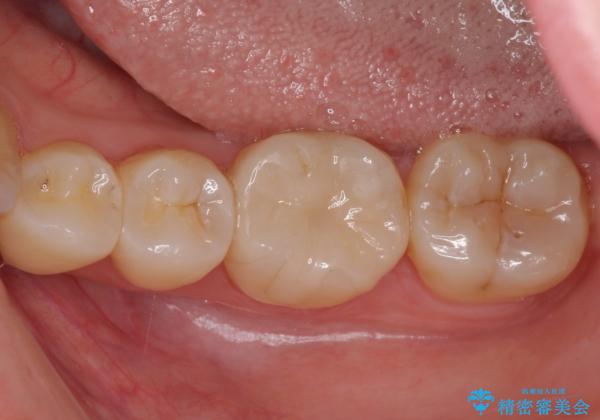

- 下の奥歯(右下7・左下7)にあって目立ってしまう銀歯を白くしたいとのことで来院された患者様です。

セラミックインレーにて修復治療を行うこととしました。

セラミックインレーを装着したことで、とても自然な仕上がりとなりました。

患者様も大きく口を開けても気にならなくなった、大変喜んでくださいました。